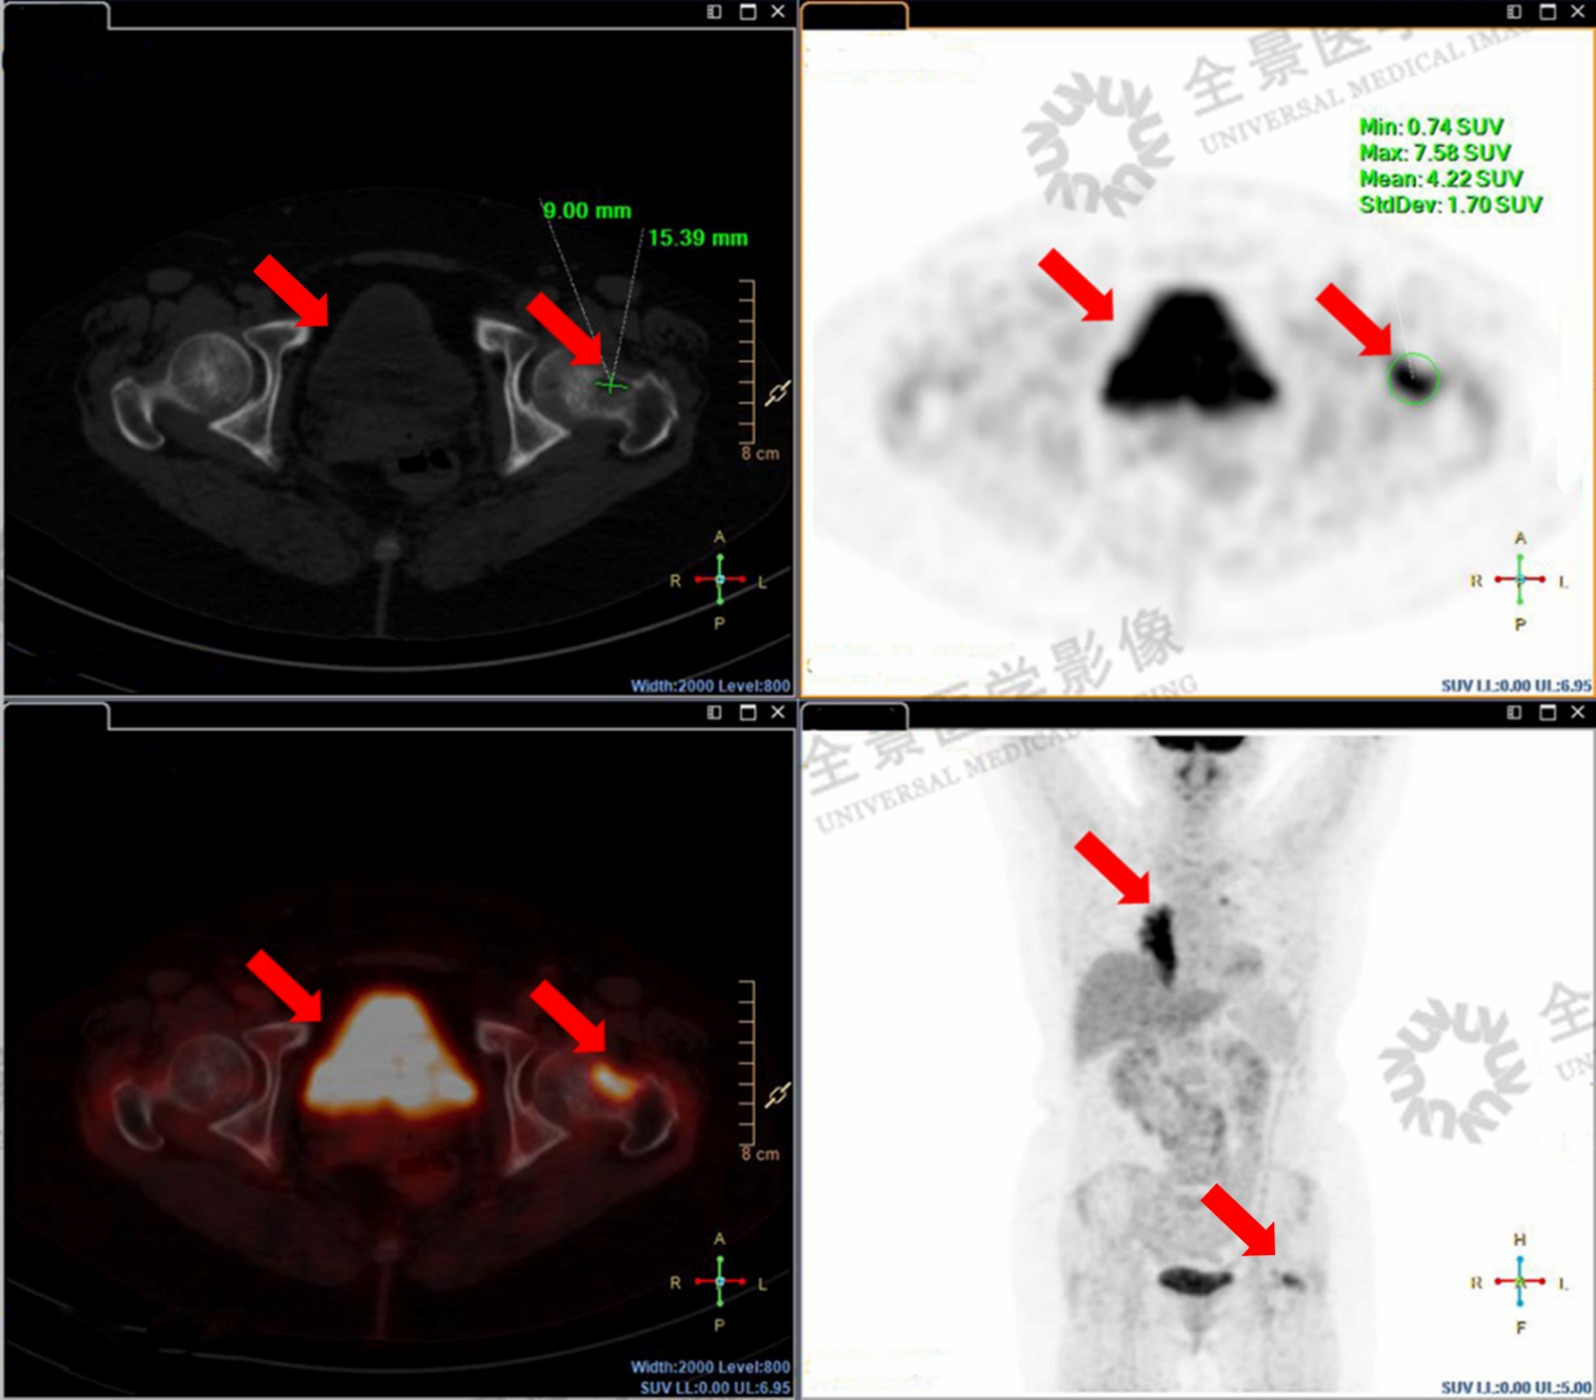

中年女性,咳嗽半年,做CT检查发现有占位性病变,但不能确定性质。通过PET/CT,发现右肺下叶肿块,在双侧肺门淋巴结、左侧股骨颈、脑部等多部位有代谢异常增高区域,考虑多处转移。

左股骨颈骨质破坏